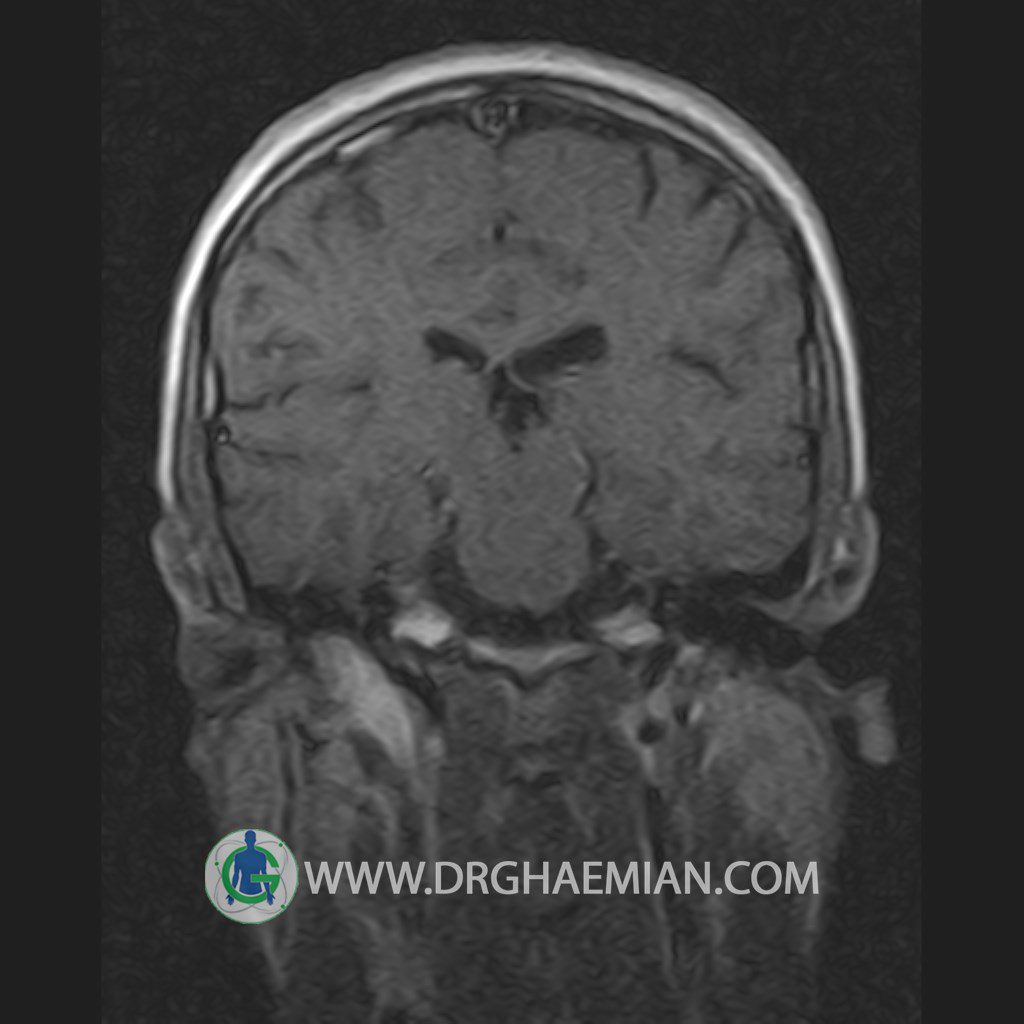

پزشکان اغلب از تصویربرداری ام آر آی برای تشخیص و درمان عارضه های پزشکی که فقط با استفاده از اشعه ایکس یا میدان مغناطیسی و امواج رادیویی قابل مشاهده است، استفاده می کنند. دستگاه ام آر آی تصاویر دقیق از ساختار های داخلی بدن ایجاد می کند. در این کیس یک میکروآدنوم در هیپوفیز بیمار مشاهده می شود.

HYPOPHYSIS MRI

(with and without contrast)

Technique: Axial , coronal T1 , Axial , coronal , sagittal T2 , Axial, coronal T1 post Gd & 64 dynamic thin coronal slices.

REPORT :

The infundibulum is centered and of normal size .

The optic chiasm and suprasellar spaces appear normal .

The cavernous sinus and imaged portions of the internal carotid artery and carotid siphon are unremarkable .

Evaluable portions of the neurocranium show no abnormalities .

The sphenoid sinus is clear and pneumatized .

Imaging of the hypothalamus after contrast medium administration was normal.

– Small hypoenhancing mass lesion ( 3 x 4 mm ) in posterior of pituitary stalk suggestive for micro adenoma

– Mucosal thickening in ethmoid & maxillary sinuses

is seen